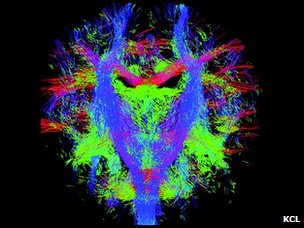

新生儿的脑神经纤维束

这张动态的脑神经路径图可以被用来按图索骥,解读不同的脑神经之间如何沟通、交流和联结的。

伦敦大学国王学院、帝国理工大学和牛津大学附属医院的儿科专家们的制图目标是希望能精确地、动态地图解脑神经信息传递线路和流程,在最细微具体的层次显示脑神经系统的发育成型过程。

这项研究的核心是MRI扫描技术的更新,使得科学家得以精确捕捉以前力所难及的胎儿脑神经系统成长的细节。